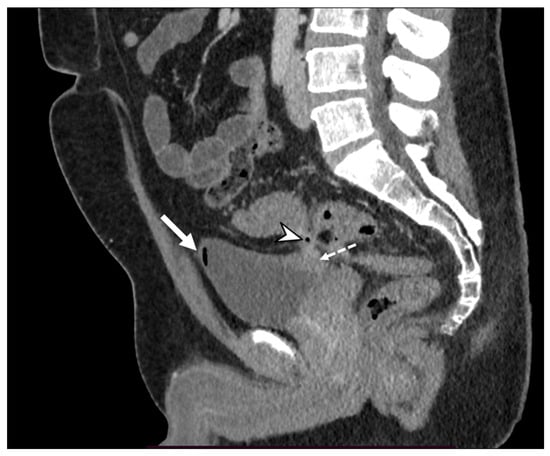

Figure 4. Axial contrast-enhanced arterial (a), portal (b), and delayed (c) CT phases show the presence of arterial active contrast extravasation within a diverticulum (arrowheads), more appreciable in the later phases of the study (b,c); this is a typical finding of active bleeding. Following DSA (d,e) reveals active extravasation of iodinated contrast medium (arrow), allowing identification of the source of the bleeding, which was then treated with coil embolization (dotted arrow in (e)).

The inflammatory process could cause engorgement of the mesenteric vessels at the involved colonic tract, which is appreciated on CT images as the “centipede” sign [18]. ACD is one of the most common causes of pylephlebitis, ascending septic thrombophlebitis, characterized by inflammation and septic thrombosis of the mesenteric and portal venous systems [2,5]. Pylephlebitis represents the extension of the septic process to the efferent venous system from the inflamed bowel region [22]. CE-CT imaging shows filling defects in the mesenteric or portal vein, gas or soft tissue density within the vein (representing purulent material), and circumferential stranding of the perivascular fat can be appreciated [3]. Complications of thrombophlebitis include the development of liver abscesses, septic emboli, venous rupture, and pulmonary thromboembolism [23]. Representing the diverticulum as an outpouching from a parietal defect from where the blood vessels penetrate, diverticular bleeding can be an occurrence, more appreciable in chronic diverticulitis [3,24]. On unenhanced CT, hyperdense intraluminal contents can suggest bleeding; after contrast medium, the presence of active contrast extravasation with enlarging contrast volume on the portal venous phase represents the finding of active bleeding (Figure 4).